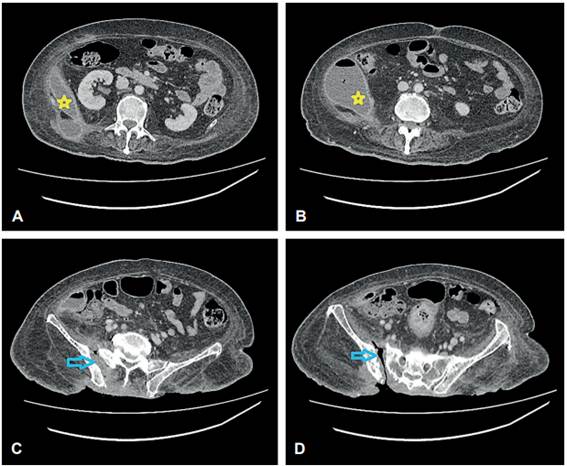

Figura 1.

Serie de abdomen donde mencionan que existe una burbuja gaseosa en el flanco y fosa ilíaca derecha, sugestiva de neumoperitoneo (circulo verde). Además, hay destrucción y resorción de la cabeza femoral derecha (junto a la estrella amarilla), asociado con luxación coxofemoral, y alteración en la esfericidad de la cabeza femoral izquierda, la cual presenta osificaciones heterotópicas en el espacio articular coxofemoral. Diástasis de la sínfisis púbica en aproximadamente 5 cm. Proyectil de arma de fuego localizado en el margen posterior del cuerpo vertebral T12 (flecha azul).